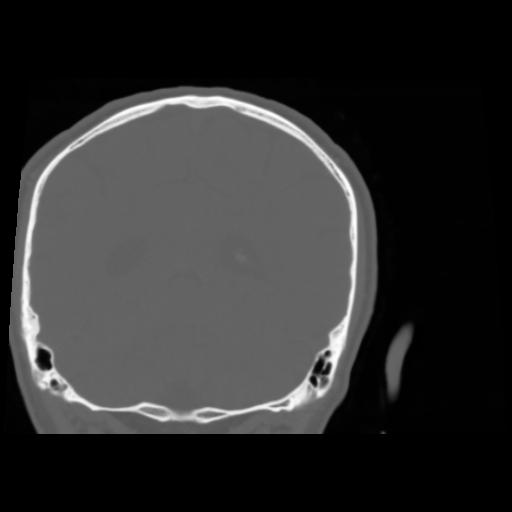

5 CEREBRO,,Coronal,3.000,CEREBRO,Coronal,